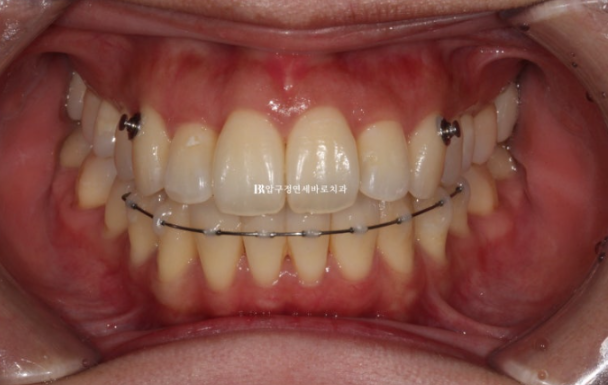

치료 시작 후 5개월째의 모습입니다.

24.07

송곳니에 붙은 것은 고무줄 거는 버튼입니다.

위 아래 견치간 폭경 밸런스를 위해 마지막 한 달 간 고무줄을 걸었습니다.

24.07 2D 설측 장치 교정

설측장치인 2D 부분교정용 장치 모습입니다.

뒤로 붙이니 교정기간 내내 보이지 않습니다.